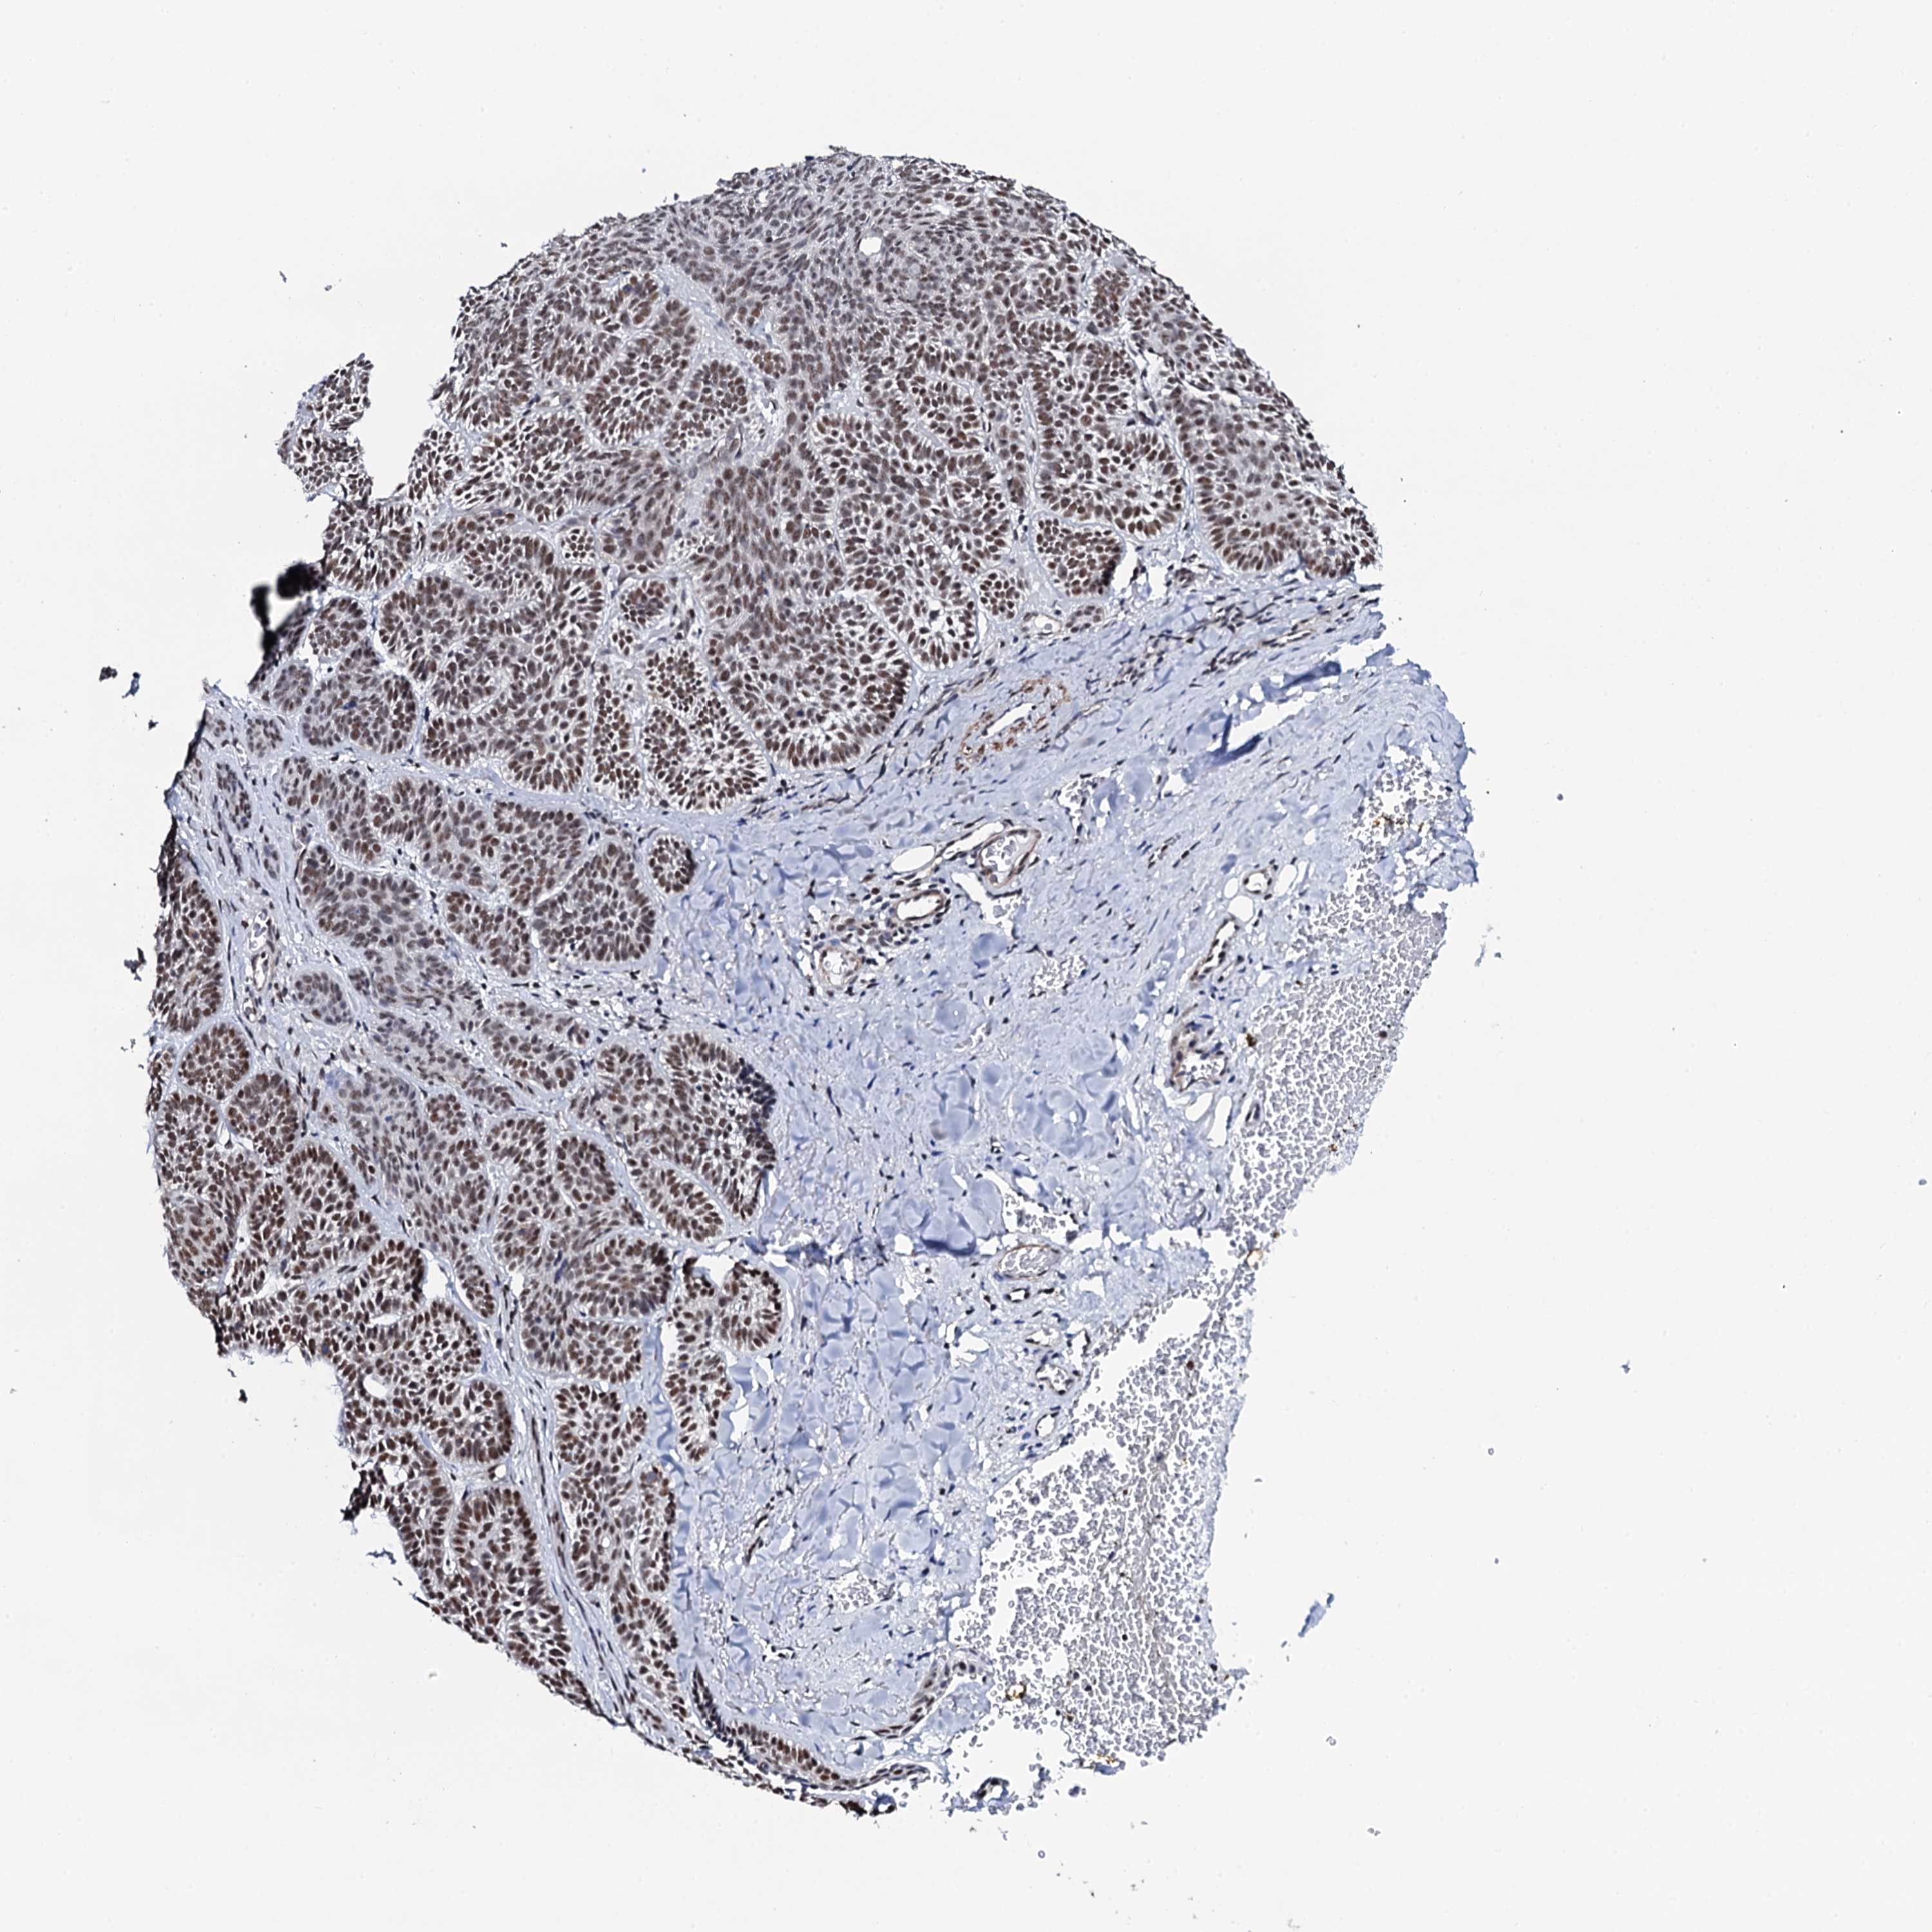

SKIN CANCER - Protein expressioni

A mouse-over function shows sample information and annotation data. Click on an image to view it in a full screen mode. Samples can be filtered based on level of antibody staining by selecting one or several of the following categories: high, medium, low and not detected. The assay and annotation is described here.

Antibody staining in the annotated cell types in the current human tissue is reported as not detected, low, medium, or high, based on conventional immunohistochemistry profiling in selected tissues. This score is based on the combination of the staining intensity and fraction of stained cells.

Each image is clickable and will lead to virtual microscopy that enables deeper exploration of all samples and also displays staining intensity scores, fraction scores and subcellular localization as well as patient and tissue information for each sample.

Antibody HPA039878

Staining

High

Intensity

Strong

Quantity

>75%

Location

Nuclear

Basal cell carcinoma